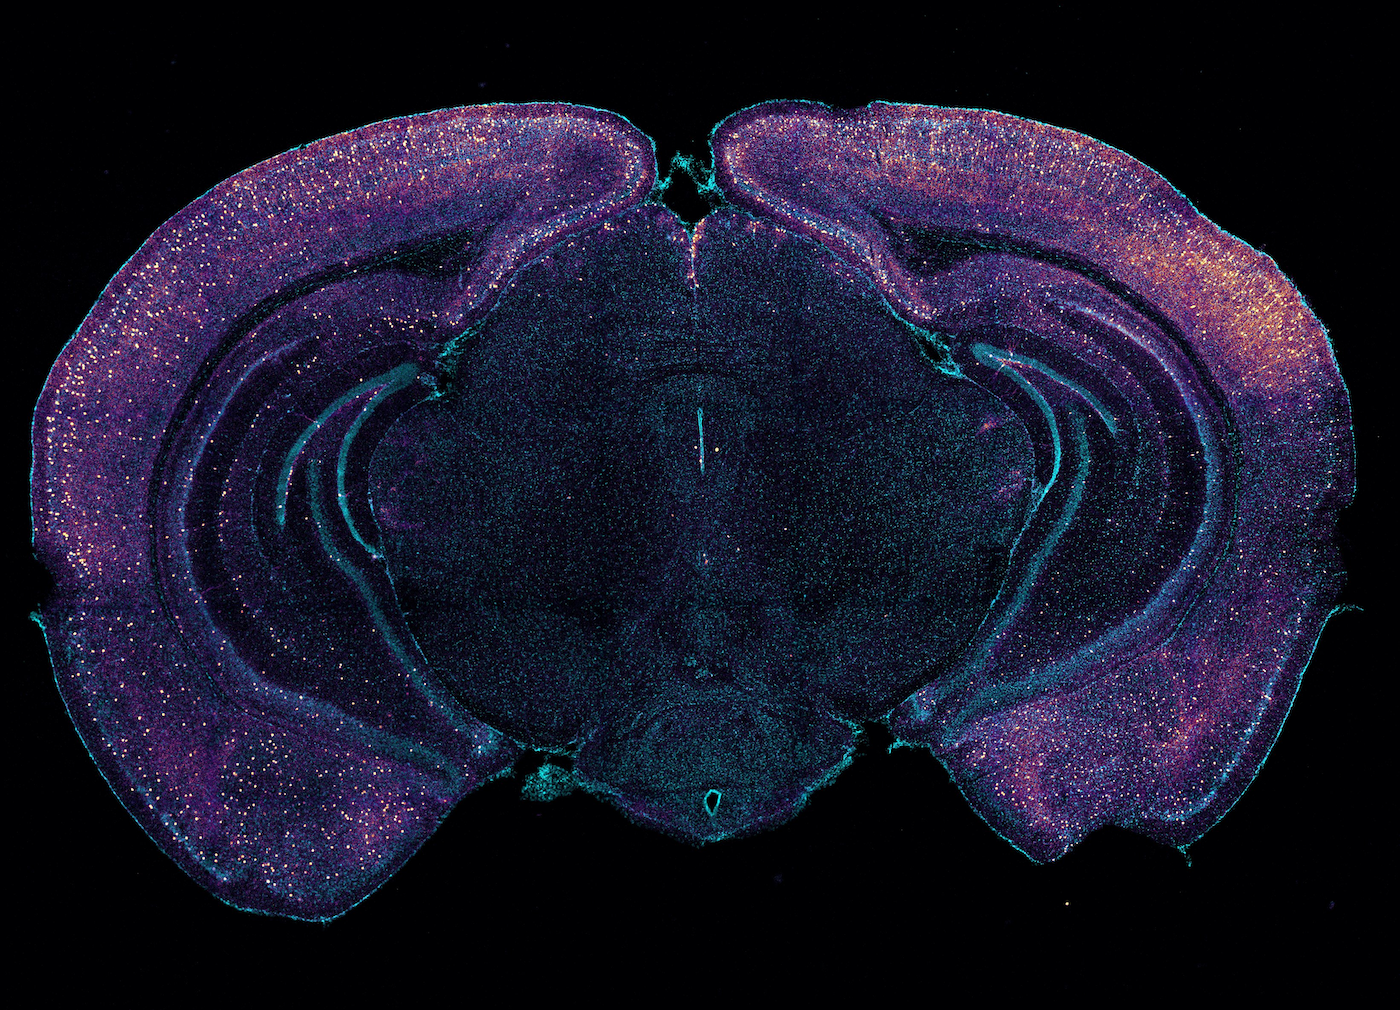

LI-HUEI TSAI: Brainwaves happened when the nerve cells in our brain fire synchronously together. So this can be detected by electrode electroencephalogram recordings. And then it will appear as waves or rhythms. And there are many different frequencies of this brainwaves. And we are particularly interested in the so-called gamma waves. And we use 40-hertz light and sound stimulation to induce gamma waves in the brain.

LI-HUEI TSAI: Right. So the gamma waves has been known to be very important for higher-order cognitive functions such as attention, sensory processing, learning, and memory. And it turned out that in Alzheimer disease, both in human subjects and in animal models, the gamma waves are compromised. So, initially, we just wanted to boost gamma waves in the brain of Alzheimer’s animal models to see whether this can improve either function or reduce pathology.